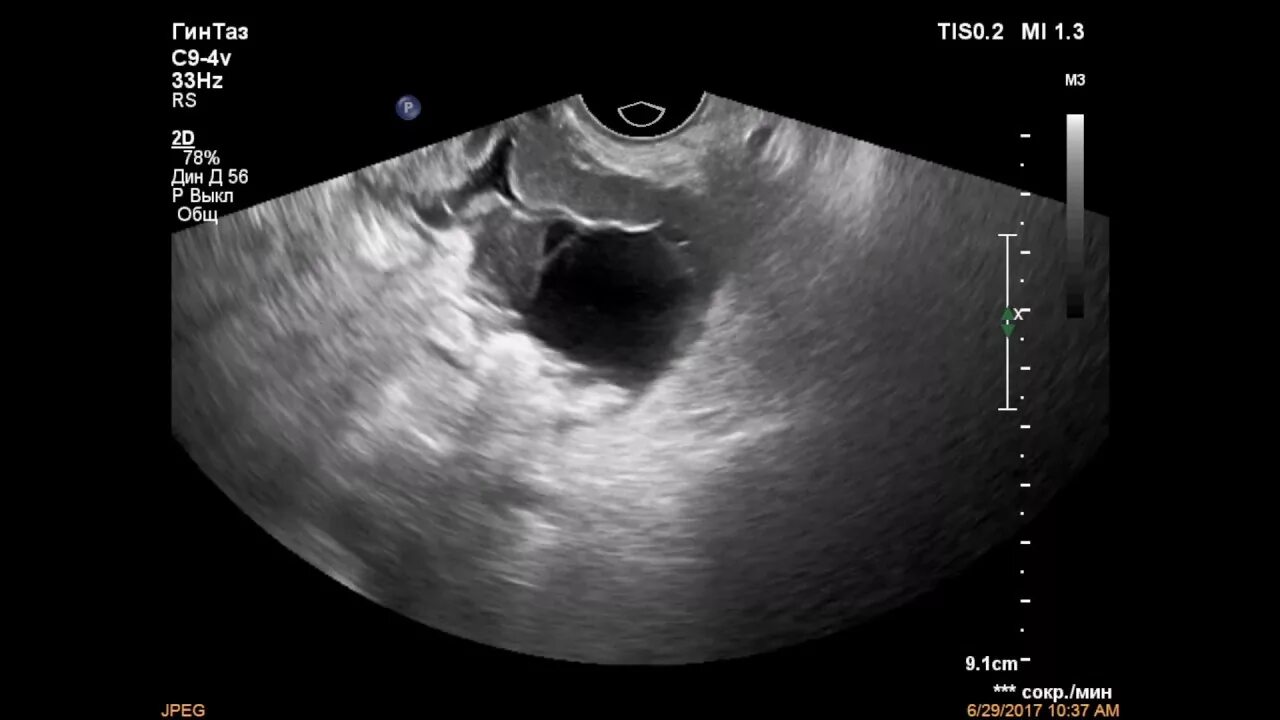

Когда делать узи яичников